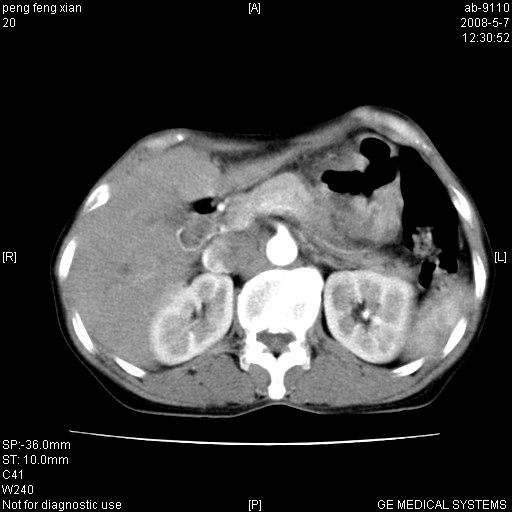

女,56岁。b超左一腹包块,考虑胃肠道肿瘤。

胃壁增厚,左前胸壁局限性隆起,考虑胃癌可能性大,建议做胃镜

典型胃癌胰体尾部受侵。

胃底占位待出;右肾结石?

胃体部胃壁增厚,不均匀性强化,与胰腺分解欠情.

考虑:胃癌,胰腺受侵待除外.

鉴别:胃淋巴瘤(强化不明显)

建议:胃镜检查.